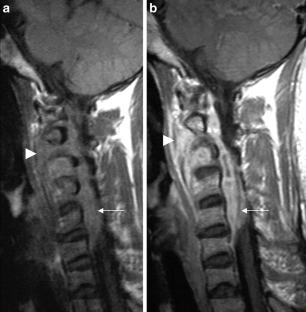

The CNS TB can be manifested (1) diffuse as tuberculous meningitis (TBM), (2) localized as tuberculoma or (3) tuberculous abscess or (4) in extradural and intradural spinal infections. Information on clinical presentation, underlying pathology and the distinguishing features is demonstrated. The TBM is further described, which may lead to cranial nerve palsy, hydrocephalus and infarction due to associated arteritis of the basal perforators. The differential diagnoses are vast and include other infections, such as bacterial, viral or fungal meningoencephalitis, malignant causes or systemic inflammation with CNS. Complicating factors of diagnosis and treatment are HIV coinfection, multi-drug resistance and TB-associated immune reconstitution inflammatory syndrome (IRIS).

Garg RK, Malhotra HS, Gupta R. Spinal cord involvement in tuberculous meningitis. Spinal Cord. 2015;53:649–57.